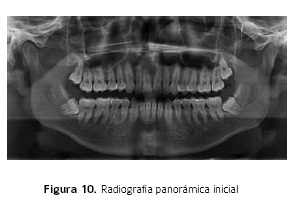

Análisis Cefalométrico

Clase II Intermaxilar moderada, retrognatismo inferior moderado, micrognatismo inferior moderado, macrogenie leve, biotipo dolicofacial, rotación horaria mandibular (Figuras 9,10).